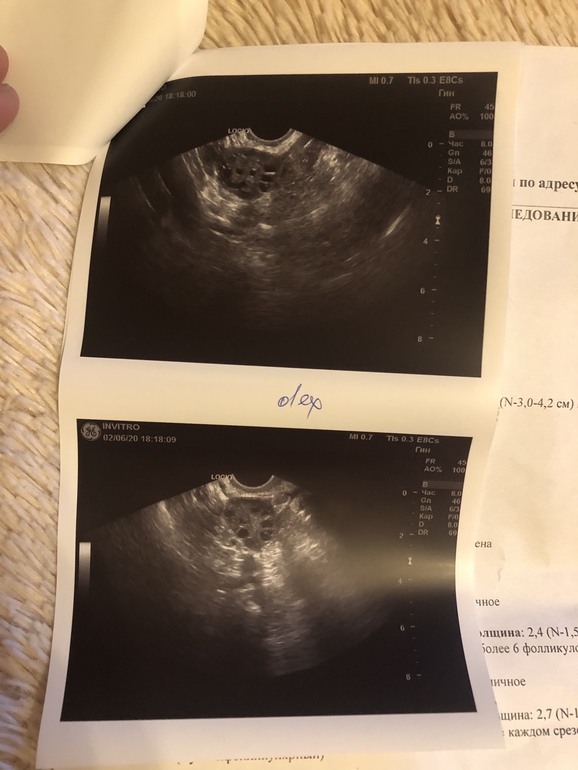

Про эндометрий ничего не сказала, но он тонкий, как я понимаю. это нормально для этого дц?

Эндометрий маловат, но не критично. Нормально средняя нормально 12